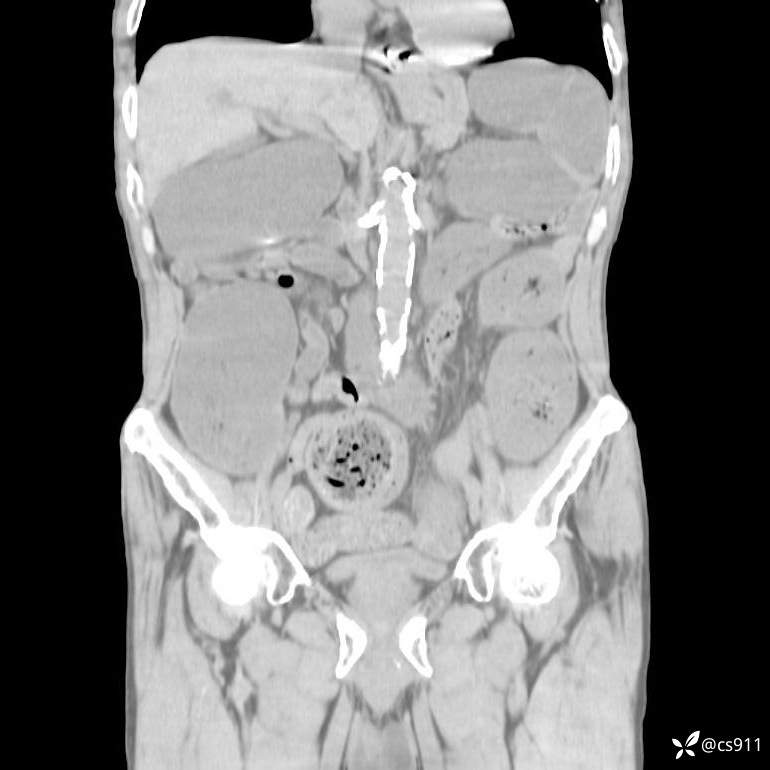

急腹症之急诊CT,原因?答案公布

男,77岁,腹痛、腹胀伴恶心呕吐1天。呕吐胃内容物,非喷射性呕吐,有咖啡色样胃内容物,诉有胃穿孔病史。查体:全腹平,下腹部压痛,全腹无反跳痛,叩诊呈浊音,移动性浊音阴性,肠鸣音减弱,1-2次/分。肛检:直肠未扪及明显肿物,可触及大量粪块。

T 36.6℃ P 80次/分 R 26次/分 BP 100/60mmHg

白细胞(WBC) H 14.55 10e9/L 4-10

中性粒细胞百分率(NEUT%) H 85.7 % 40-75

血淀粉酶(AMY) HH 1859 U/L 35-135

癌胚抗原(CEA) H 27.44 ng/ml 0-5

呕吐物 潜血试验 * 阳性 阴性

患者轮椅入室检查神志清楚, 能配合摆位和呼吸